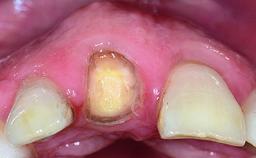

Abutment Type CAD/CAM

Prosthesis Type FDP

Retention Cemented, with prosthesis margin < 3mm submucosal Cemented, with prosthesis margin < 3mm submucosal